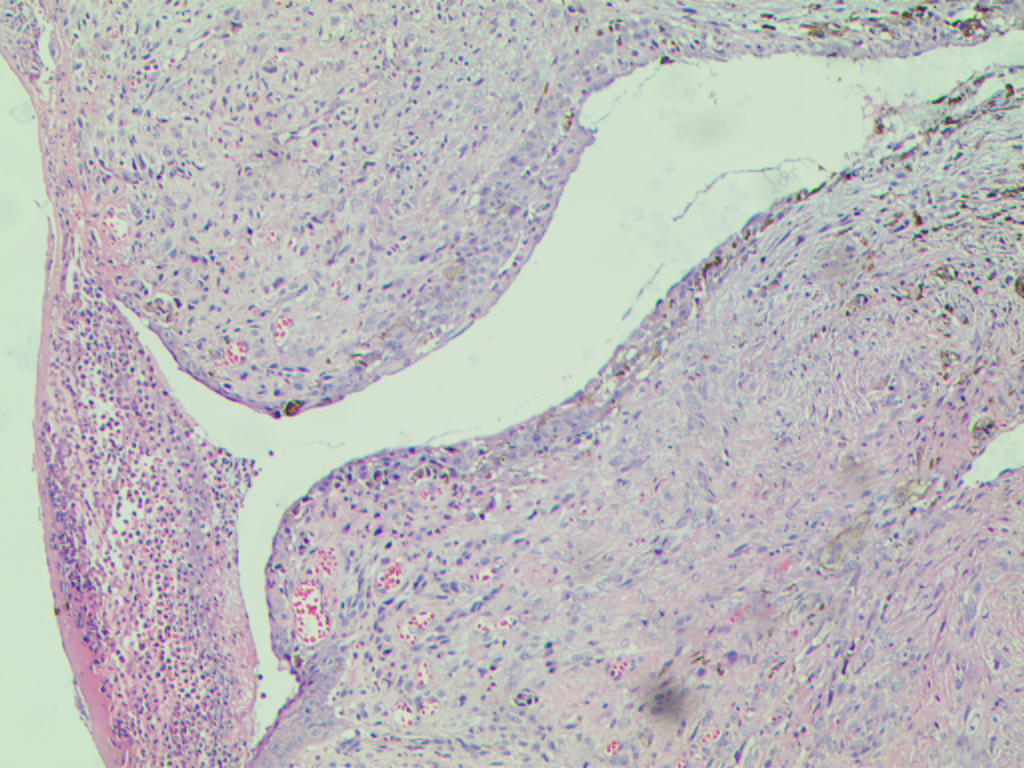

组织学上千变万化,交界区及及表皮浸润可提示肿瘤原发,常见表面溃疡,骨及软组织浸润。

生长方式多种,可呈上皮样、实性、器官样、片状、巢状及乳头状结构,束状、交叉簇状、席纹状及血管外皮瘤样,脑膜上皮样;

细胞形态多样:未分化、上皮样、小细胞、浆样细胞、横纹肌样及巨细胞样均有可能见到;核空泡样,但有时染色深,可见显著的、不规则的嗜酸性大核仁;常见核内浆样包涵体;核分裂像易见,并可见非典型核分裂像;肿瘤细胞常含有色素;常可见坏死;

少数病例可见促结缔组织增生性纤维化;外周神经浸润提示预后差。